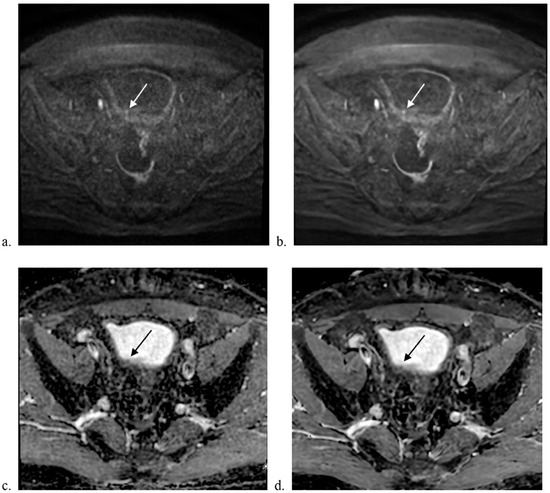

3.2. Qualitative Image Analysis

3.3. Quantitative Image Analysis